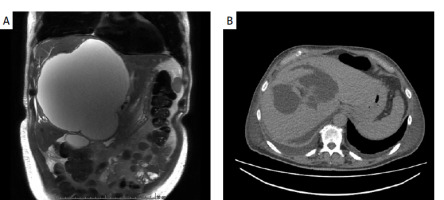

A 68-year-old man with benign prostatic hyperplasia was admitted to the hospital with fever of up to 40°C persisting despite oral antimicrobial therapy. In 2023, the patient had been diagnosed with an extensive liver cyst measuring 13 × 15 × 17.5 cm. The patient had no history of invasive medical procedures. An artist by profession, among other things he made sculptures in clay. On admission to our department, the patient was in good general condition, with no jaundice; the abdomen was soft and nontender. An extensive pathological mass was palpable in his epigastric area. Laboratory tests revealed: alanine transaminase (ALT) 65 U/l, total bilirubin 19.6 µmol/l, γ-glutamyl transferase (GGT) 292 U/l, white blood cells (WBC) 12 G/l, C-reactive protein (CRP) 254 mg/l. Given the suspicion of liver cyst infection, an abdominal magnetic resonance imaging (MRI) scan was obtained, revealing a cyst in the right liver lobe measuring 16 × 18 × 20 cm with a contrast-enhancing capsule – an abscess, with dilatation of intrahepatic bile ducts in both lobes (Figure 1 A). In addition, features of gallbladder adenomyomatosis were observed. After blood cultures were collected, the empirical therapy with piperacillin and tazobactam was administered. On the 5th day of hospitalization, a percutaneous drainage was performed under ultrasound guidance, yielding a total outflow of about 4000 ml of purulent contents, followed by biliary contents in the drain. A pus culture showed growth of R. planticola, resistant to ampicillin. In the following days of hospitalization drainage of a significant amount of biliary contents, at about 1500 ml/day, persisted. On the 11th day of hospitalization, an abdominal computed tomography (CT) scan was obtained, revealing two-banded irregular fluid reservoirs in segments IV, VIII, and V, measuring 9 × 14.5 × 6.5 cm, and a thickened capsule with a small gas bubble, consistent with a residual abscess (Figure 1 B). Laparoscopy with intraoperative ultrasound evaluation was performed: the fluid lesions were drained, and pigtail drains were left in each lesion. Because of persistent drainage of bile, the patient underwent two endoscopic retrograde cholangiopancreatography (ERCP) procedures – because of a leak of bile from the left hepatic duct, a prosthetic device was inserted into it and the common bile duct. The patient was discharged home in good general condition.

A – Abscess of the right lobe of the liver: magnetic resonance imaging before treatment; B – status after abscess drainage, fluid spaces visualized – computed tomography image